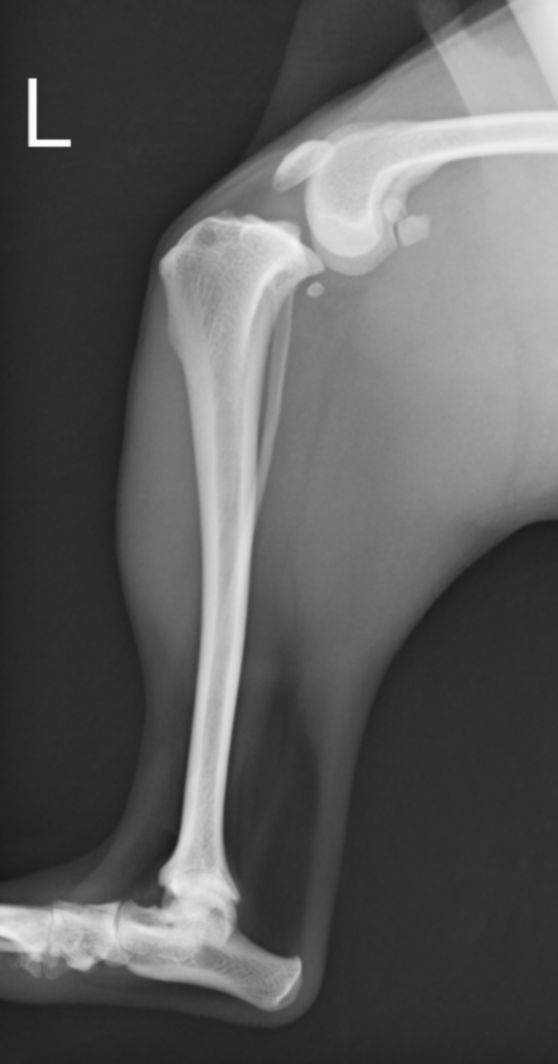

前十字靭帯損傷の膝。大腿骨が尾側に滑り、脛骨の前方変位が認められる